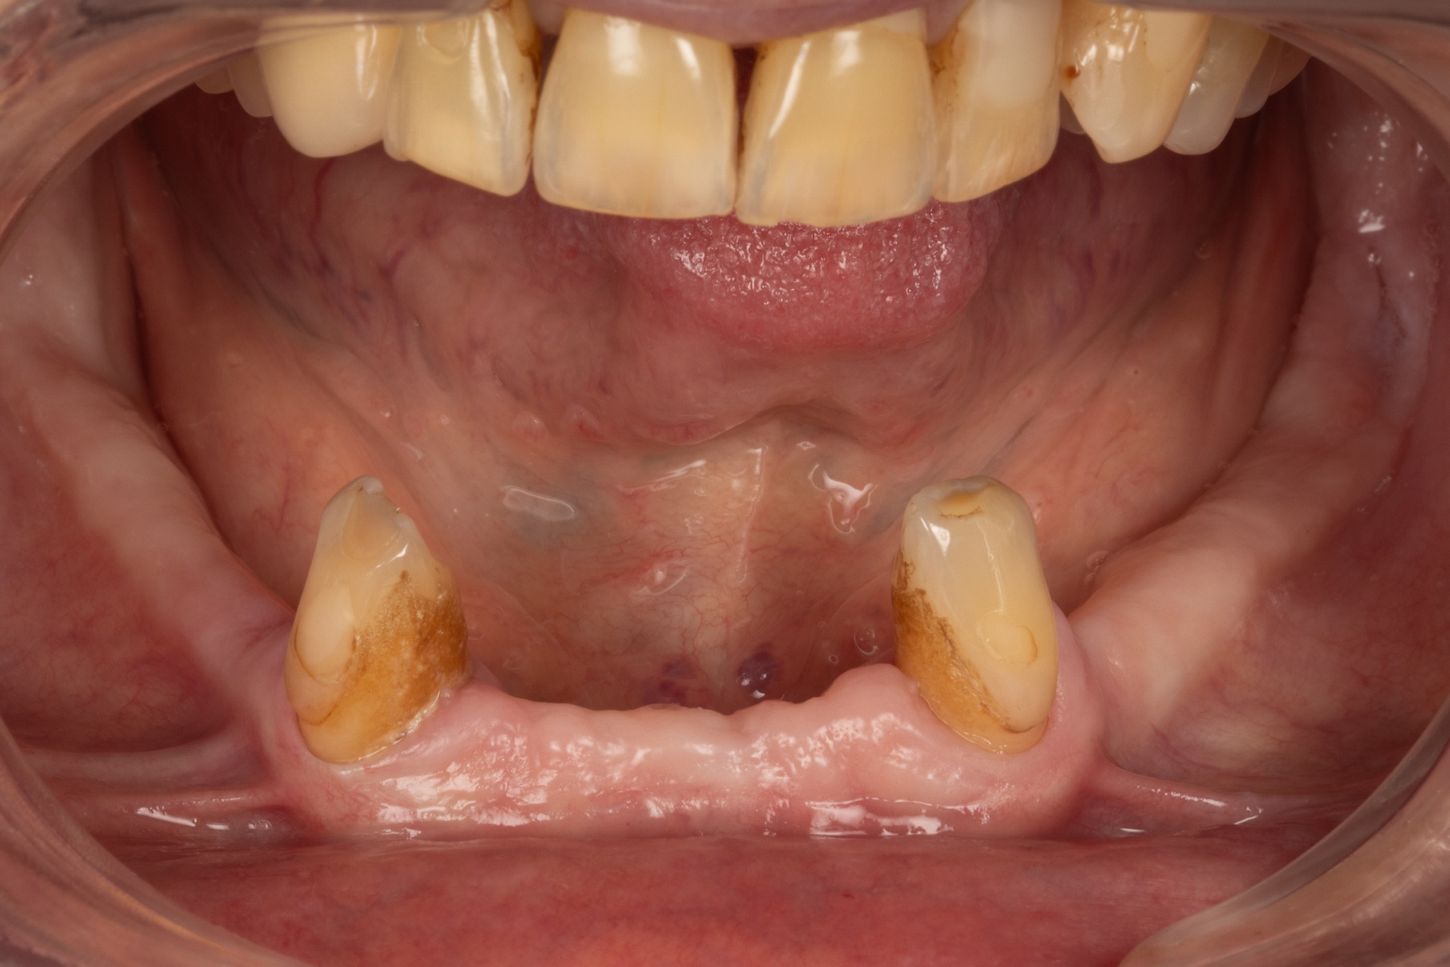

2c. Situation in the mandible: thin alveolar crest and residual teeth 33 and 43.

2c